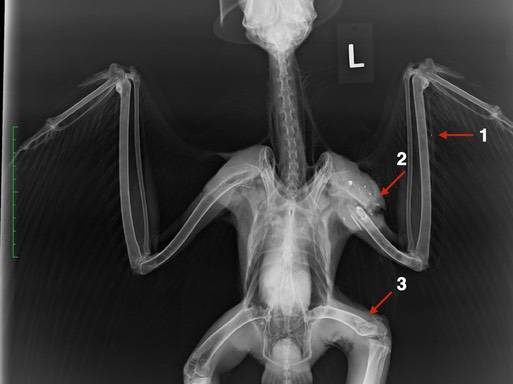

Two of the Red-tailed Hawks had both humerus and femur fractures. One was shot, the other was hit by a car. In the first radiograph the arrows point to damage caused by one projectile. If you look closely, you will see a tiny metal fragment at the tip of arrow one. Many metal fragments and a humerus fracture are visible at arrow 2. Although there are no metal fragments visible at arrow 3, necropsy results indicated the projectile was responsible for the femur fracture. The arrows in the second radiograph point to the humerus and femur fractures caused by the bird being struck by a vehicle.